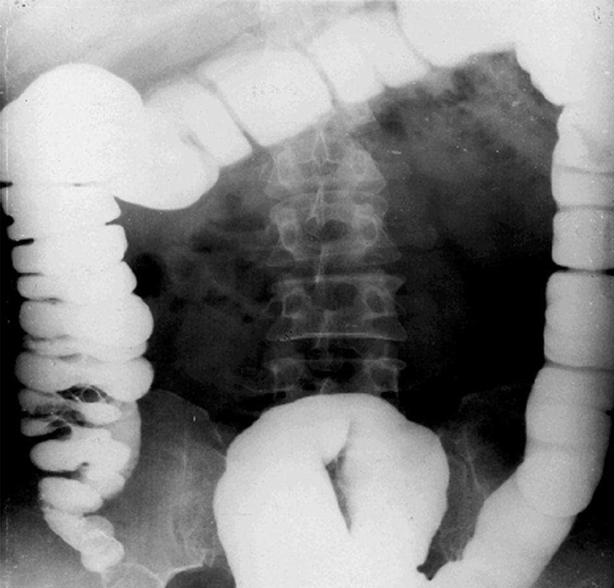

急性小肠梗阻:小肠扩张积气,小肠腔内积液,结肠内气体少。